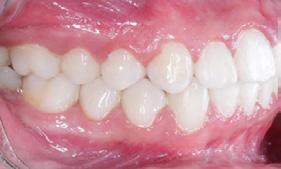

Fotografías en la lateral derecha tenemos: relación molar clase I bilateral y relación canina clase I bilateral, líneas medias dentales coincidentes (Figura 3), -5 mm de overjet, 10% de underbite, las arcadas superior e inferior son ovaladas, apiñamiento severo superior e inferior (Figura 4).

Figura 3. Intraorales frente, lateral derecha e izquierda. Figura 4. Intraoral oclusal superior e inferior.